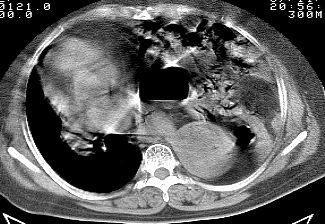

标题: CT10753:女, 64岁 隔疝 [打印本页]

标题: CT10753:女, 64岁 隔疝

女, 64岁 三十年前胸部外伤史, 间断胸闷,

典型左侧膈疝,疝出物为胃和大网膜,纵隔右移

同意左侧膈疝,不过,有过外伤史,左肺有受压征象,同时有胸膜增厚。

典型左侧膈疝,如此严重少见。